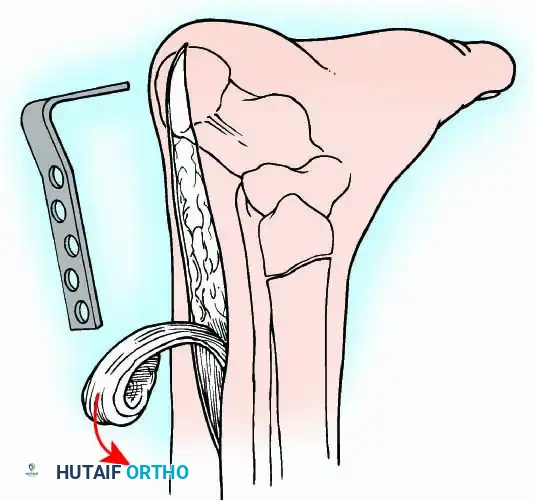

Transmalleolar (Transfibular) Approach

This approach utilizes a lateral incision over the distal fibula. A transfibular osteotomy is performed, reflecting the distal fibula distally or excising it entirely to be used as autograft. This provides unparalleled exposure of the lateral half of the joint and the posterior facet. It is highly effective for correcting severe varus/valgus deformities. A supplementary medial incision (medial malleolar osteotomy) can be added for complete joint exposure.

For complex hindfoot reconstructions, specialized plating systems, including anterior or lateral locking plates, can be utilized to supplement screw fixation, particularly when structural allografts are required to restore limb length.